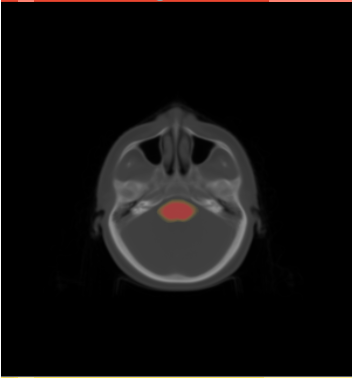

- We have 20 datasets for H&N including lungs and chests. For example

- We selected the ROI of every data excluding lung and chest. For each data there exist the segmentations of brain stem, left and right parotids. For example

- We constructed the average atlas of 20 datasets of ROI, and merged the segmentations into the average atlas. These segmentations are the probability maps of

brain stem, left and right parotids.